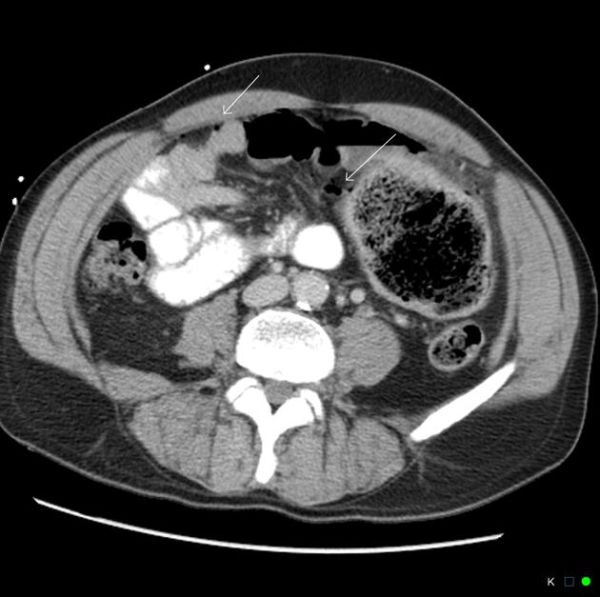

(PDF) Ischemic Colitis Medical Differential, Radiologic Diagnosis, and Ischemic Colitis Wikem Patients with colitis present with watery diarrhea, abdominal pain, tenesmus, urgency, fever, tiredness, and. This segment of the large intestine is. Wikem mobile app has been decommissioned. Defined as a reduction of blood to the small and/or large intestines. May be acute or chronic. Colitis is common and increasing in prevalence worldwide. Navigation, search contents 1 background 2 clinical features. Ischemic Colitis Wikem.